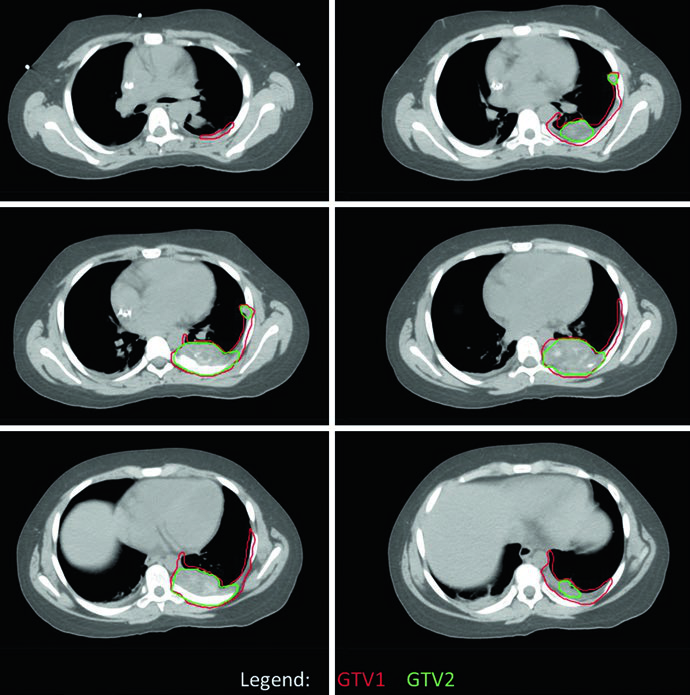

O planejamento no EWS utiliza dois conjuntos de volumes: um baseado na extensão da doença ao diagnóstico (GTV1/CTV1) e outro definido pela doença residual pós-quimioterapia e, eventualmente, pós-cirurgia (GTV2/CTV2). As margens adicionadas aos CTVs para incerteza de posicionamento resultam nos respectivos PTVs.

| GTV1 | Extensão pré-quimioterapia da doença macroscópica (osso e partes moles), incluindo linfonodos suspeitos não ressecados. O GTV1 pode ser modificado se o tumor inicial se estendia para cavidades corporais (pelve, tórax) e houve regressão com quimioterapia. |

| GTV2 | Tumor residual após quimioterapia de indução; contudo, toda extensão óssea pré-quimioterapia é tipicamente incluída no GTV2. No pós-operatório, o GTV2 corresponde à doença residual (óssea ou de partes moles) e sítios de margens positivas. |

No caso de EWS de parede torácica, a simulação com TC de quatro dimensões (4DCT) foi realizada para capturar a excursão respiratória completa dos volumes-alvo. O tumor original ocupava a metade posterior do hemitórax esquerdo, mas o GTV1 foi adaptado para refletir o “pushing” tumoral no espaço agora ocupado por pulmão normal. A cobertura dos sítios de contato e envolvimento originais foi mantida. Da mesma forma, PTV1 recebeu 45 Gy e PTV2 um boost adicional de 10,8 Gy.